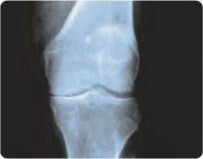

STAGE 1

Mild decrease in Joint Space